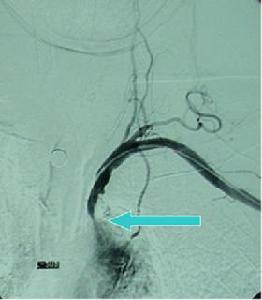

(1)CT掃描:可顯示腦皮質和腦白質內多發的大小不等低密度梗死灶,側腦室體旁暈狀低密度區腦白質疏鬆症(leukoaraeosis)和腦萎縮等。

(2)MRI檢查:可見雙側基底核腦皮質及白質內多發性T1WI低信號、T2WI高信號,陳舊病灶界限清、信號較低無明顯占位效應新鮮病灶界限不清信號強度不明顯,早期T1WI改變可不明顯T2WI可顯示病灶;病灶周圍腦組織局限性腦萎縮或全腦萎縮

腦梗死大小、部位與痴呆:過去,進行性腦功能衰退所致的痴呆被人認為是腦動脈硬化所致的腦缺血、缺氧引起,但近年來臨床研究已明確,真正的腦血管痴呆是由於多次發作的腦梗死所致的腦組織累積性損害,故亦稱多梗死性痴呆(MID),病理檢查已證實MID患者有足夠的腦組織損害才能產生痴呆,多數人認為梗死灶體積與痴呆的嚴重程度有密切關係,梗死灶體積越大越容易引起痴呆。梗死灶容積>50ml可以合併痴呆,>100ml則經常合併痴呆。而本組結果大面積腦梗死占17.4%,小梗死灶占82.6%,多發病灶占95.6%,提示病灶體積小也可以發生痴呆,尤其是梗死數目越多,痴呆發生率會越高,所以雙側、多發病灶、皮層病灶、體積大的病灶與痴呆關係密切。其次我們認為MID基底節區發生率高(67.4%)是由於基底節區梗死多屬於分水嶺腦梗死,梗死部位主要是頸內動脈系統及深穿支小動脈終末供應區,側支循環差。當高血壓、腦動脈硬化等腦血管病變時,使動脈壁彈性減退,動脈內膜粥樣斑塊形成,造成管腔狹窄以至閉塞,導致多發性小灶梗死發生。此部位病變導致痴呆的原因可能為:基底節處核與核之間,各核與皮層之間有廣泛的纖維聯繫,許多纖維與記憶和認識功能有關,如受破壞即可出現痴呆,特別是主側半球腦的損害可導致痴呆。從而表明腦梗死部位、大小、範圍與痴呆有密切關係。